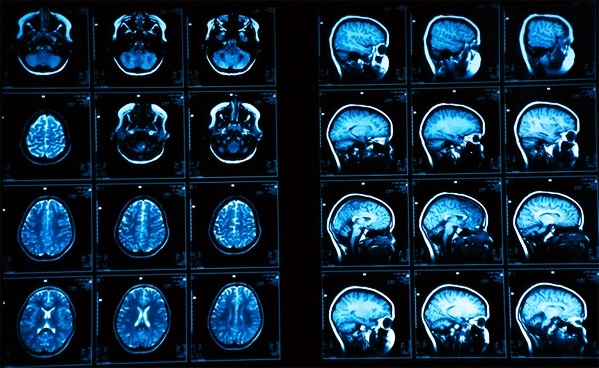

Данная диагностика разработана для изучения всех структур и отделов мозга: мозжечок, гипофиз, зрительные отделы затылочной доли, желудочки мозга, отделы, отвечающие за память и мышление.

Что покажет МРТ снимок? В расшифровке содержится информация про:

- скорость кровяного потока;

- жидкость в канале спинного мозга;

- степень диффузии тканей;

- активность коры головного мозга во время влияния различных раздражителей.